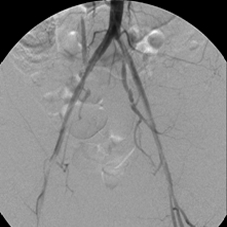

This 41-year-old woman smoked for a long time and developed severe bilateral calf cramping after short walks. Investigation revealed that she had completely occluded her distal abdominal aorta and her right and left iliac arteries, severely restricting the flow of blood into her lower limbs. She was unwilling to have surgery and came to me for minimally invasive treatment. By dripping urokinase (a clot dissolver) over 72 hours through two catheters that I advanced across the occlusions and later stenting the opened arteries, I wholly restored blood flow through her iliac channels. She walked again – without cramps.